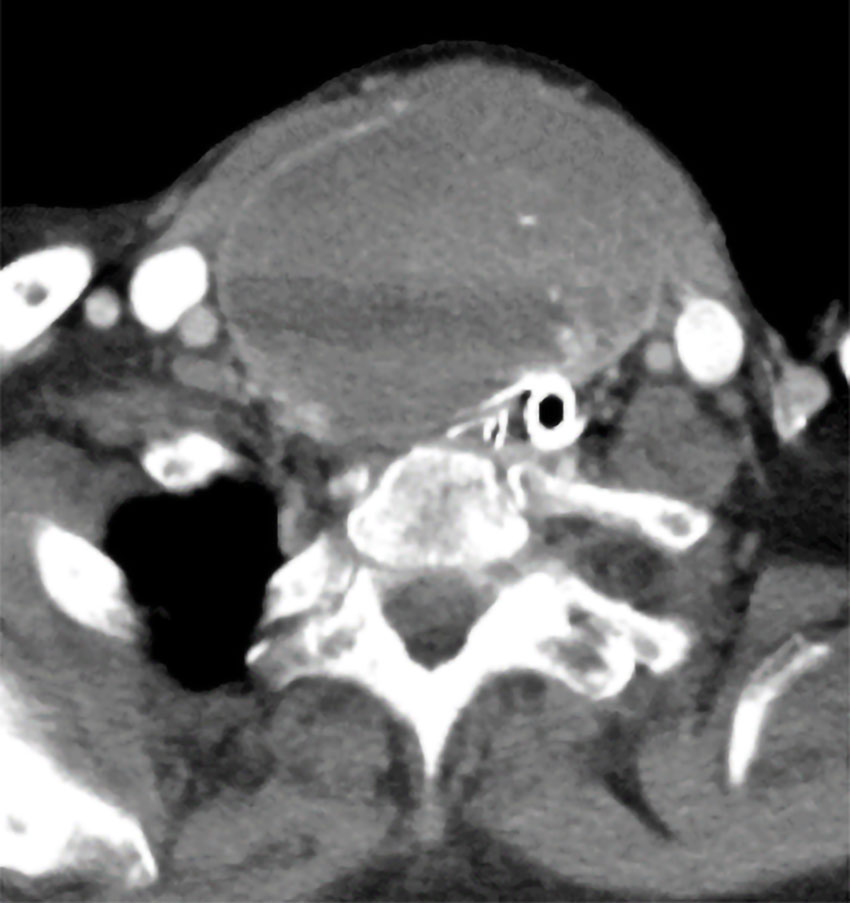

Kontrastforsterket aksialt CT-bilde av halsen viser stor oppfylling i relasjon til høyre tyreoidealapp med diameter 8 cm (og 10 cm kraniokaudal utbredelse fra nivå med C4/C5 til Th2/Th3). Trakea er betydelig komprimert og dislokert posterolateralt mot venstre (pasienten er intubert). De cervikomediastinale blodkarene synes upåvirket.

Pasienten var en kvinne i 80-årene som ble innlagt med akutt dyspné oppstått i forbindelse med trening. Anamnestisk ble pasienten utredet for et godartet struma flere tiår tilbake. Strumaet hadde siden økt i størrelse, men hun hadde vært uten symptomer fra luftveiene fram til det aktuelle.

Grunnet uttalt inspiratorisk stridor kombinert med stort struma, ble pasienten vurdert til å ha truet luftvei. Hun ble umiddelbart tatt til operasjonsstue og endotrakealt intubert (tube størrelse 7) i våken tilstand via fleksibelt skop, med beredskap for nødtrakeotomi og koniotomi under prosedyren. Man fant betydelig subglottisk trakealstenose med kun få millimeters lumen, noe som gjorde intuberingen vanskelig.

Pasienten ble deretter respiratorbehandlet på intensivavdeling og undersøkt med CT collum i påvente av kirurgi. Hun ble dypt sedert og muskelrelaksert for å minimere risiko. Påfølgende dag ble det utført ukomplisert høyresidig hemityreoidektomi, der trakea ble frigjort og vurdert som åpen og stabil. Pasienten ble ekstubert på operasjonsstuen og utskrevet fra intensivavdelingen i velbefinnende etter to dager.